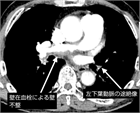

1. CTEPHの確定診断は、胸部造影CTあるいは肺動脈造影の慢性血栓所見と、右心カテーテル検査で、肺動脈楔入圧が正常(≦ 15 mmHg)な肺高血圧症(ガイドラインでは、平均肺動脈圧>20 mmHかつ肺血管抵抗>2 WU、指定難病認定基準では平均肺動脈圧 ≧ 25 mmHg)を確認する。